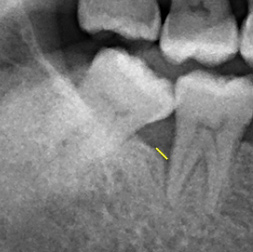

检查:患有严重牙周病问题,牙结石堆积,右下第七颗大臼齿齿槽骨严重流失

黑影区域为齿槽骨被牙结石及细菌严重侵蚀,齿槽骨被细菌侵蚀后的高度显示出骨头降低程度至牙根尖处。